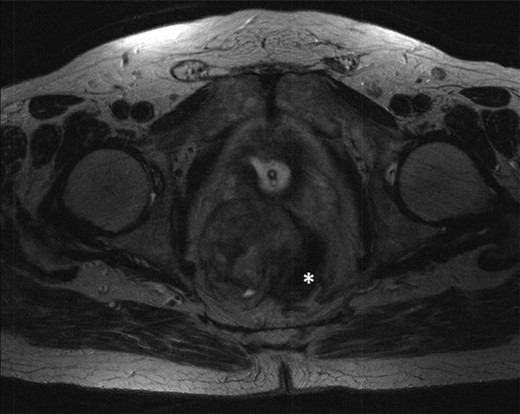

The multidisciplinary team review advised neoadjuvant treatment with imatinib mesylate and further reassessment. Repeat MR pelvis and staging PET CT abdomen, thorax and pelvis were then performed. These showed a large extra-luminal tumour with downsizing in tumour bulk (6 × 5.7 × 5.4 cm) (Figs 3–5) but in close approximation with the right seminal vesicle.

T2-weighted axial images after 3 months of imatinib mesylate therapy. The mass has shown a significant reduction in size (white star).